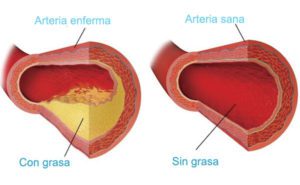

Es un tratamiento endovenoso con una solución que remueve toxinas a través de la orina, su principal componente activo es el EDTA (Acido Etilen Diamino Tetraacético). Restaura la elasticidad de las arterias al disminuir el endurecimiento producido por la oxidación, así como disminuir la actividad cancerígena formada por radicales libres, disminuyendo la mortalidad por cáncer en un 90%.

También al eliminar el exceso de calcio de las arterias, el organismo lo aprovecha para remineralizar el hueso, en promedio el aumento de masa ósea en un año es del 15%.